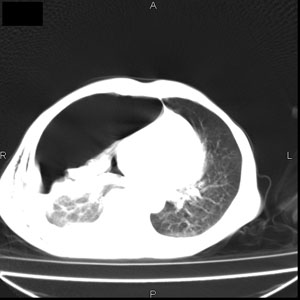

患者男,77岁,于3日前从树上摔下,头部查ct示蛛血,硬膜下出血,上腹部ct未见明显异常,右侧胸腔积液,左侧如常。肺部拍片示右侧肋骨多发骨折住院后今日来查肺部ct,我看到的是1。右侧胸腔血气胸并右肺上叶,中叶压缩性肺不张,2。右肺下叶肺挫伤并多发肋骨骨折,肌内及皮下积气3。左侧少量胸腔积液,我想请教的是3天前左侧胸腔里没有积液今天怎么出现了呢,是什么原因呢?请讨论。

因为3天前病人刚摔的时候,左侧胸腔受伤不严重,故而当时没有胸腔积液,但病人受到这么大的伤害,胸膜腔内的液体动态平衡肯定会受到影响,所以过一段时间后才出现胸腔积液。

1、外伤出血需要一定的时间

2、气胸存在时间长了,产生的胸膜渗液